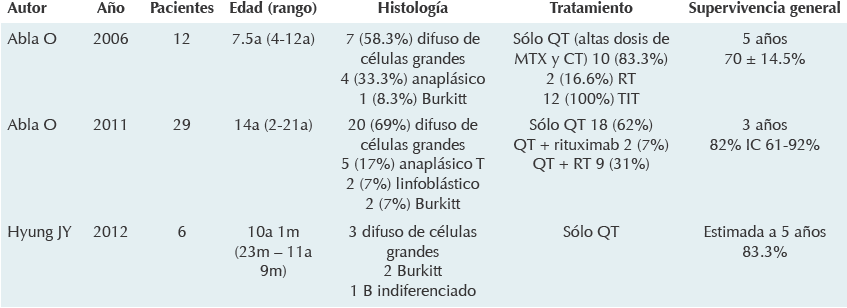

Niña de diez años, diez meses de edad, cuyo padecimiento tenía un mes de evolución e inició con vómito y ataque al estado general, se le trató como enfermedad acidopéptica sin mejoría. Tiempo después, la paciente presentó alteración de la marcha, por lo que se realizó tomografía axial computada de cráneo que mostró una zona hiperdensa en el cuarto ventrículo, que medía 2.5 x 3.5 cm y desplazaba rostralmente al tallo cerebral (Figura 1) La resonancia magnética mostró una lesión del cuarto ventrículo hipointensa homogénea, extraaxial, que reforzaba de forma difusa al contraste (gadolinio); sin infiltración aparente del cuarto ventrículo ni del pedúnculo cerebeloso por lo que se sospechó diagnóstico de meduloblastoma. (Figura 2) Lo anterior llevó a decidir una resección quirúrgica de la lesión en un 90% aproximadamente. Un informe transquirúrgico de patología informó de un tumor de células pequeñas, redondas y azules (Figura 3a). El informe histopatológico final fue de neoplasia maligna de estirpe linfoide con marcadores inmunohistoquímicos positivos para CD-45 (Figura 3b) y CD-20 (Figura 3c), base para el diagnóstico de linfoma difuso de células grandes B.

Figura 1 Tomografía computada; reconstrucciones axiales A) Fase simple: lesión en el interior del cuarto ventrículo, de contornos regulares, homogénea, hiperdensa. B) Fase contrastada: realce de forma leve con administración de medio de contraste (60 UH).